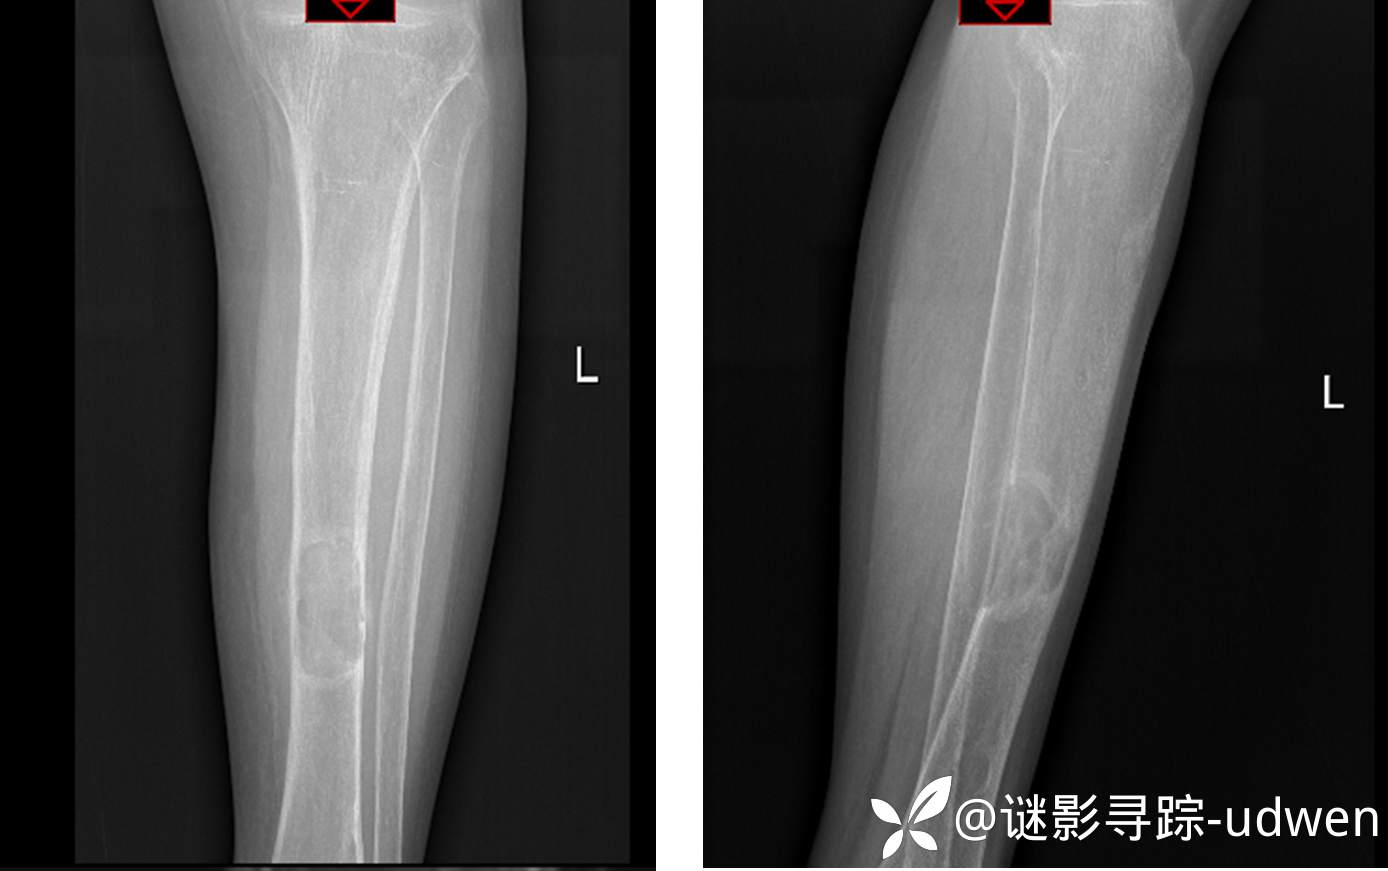

患者性别:女

患者年龄:59岁

主诉:左小腿疼痛伴活动受限半年余

简要病史:患者本人及家属诉半年余前无明显诱因出现左小腿疼痛,疼痛逐渐加重,伴活动受限,无静息痛,无发热,无头痛、头晕,无咳嗽、咳痰,无胸闷、心悸、呼吸困难,无恶心、呕吐等不适

X线